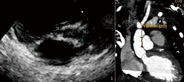

男,2岁1个月,体质量10 kg。心率增快1年,发现先天性心脏病2个月。查体:心率140次/分,心前区胸骨左缘3-4肋间可闻及3/Ⅵ级收缩期杂音。心电图示:窦性心律,左心房、右心室肥大。超声心动图示:主动脉弓中断,主动脉发育小,瓣下最窄处内径0.36 cm,瓣环0.62 cm(图1);肺动脉高压46 mmHg(1 mmHg=0.133 kPa);室间隔缺损1.7 cm,膜周融合型,双向分流;动脉导管未闭,肺动脉端0.75 cm,双向分流。血管造影示:肺动脉收缩压、舒张压、平均压为79、41、59 mmHg,升主动脉直径7.1 mm。诊断:主动脉弓中断(B型),主动脉狭窄、左心室流出道梗阻、室间隔缺损、动脉导管未闭、肺动脉高压。

术后第4天延迟关胸。呼吸机辅助114.8 h,住重症监护室5天。予以全胃肠外营养、呼吸机支持,同时应用多巴胺、肾上腺素维护心功能。术后16天复查超声心动图示:肺动脉瓣轻度反流,主动脉-肺动脉吻合口无梗阻,心房水平双向分流,管道瓣膜轻度反流。心脏CT 、三维重建示升主动脉与肺总动脉吻合口直径约11.8 cm。(图2)。